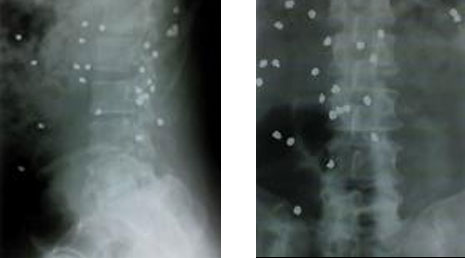

56. Spinal gunshots